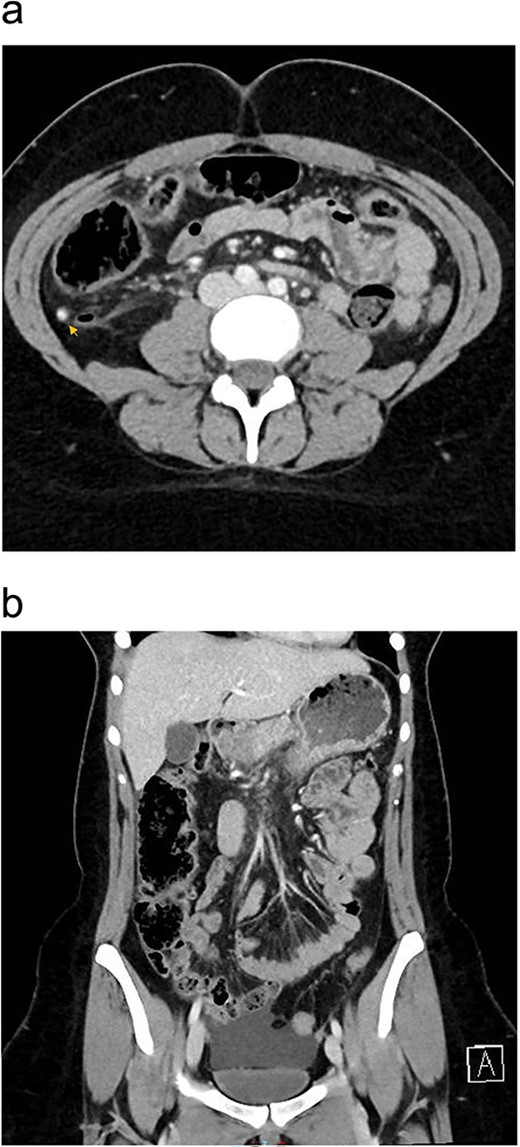

The patient was managed with a low-fat diet, octreotide, and close monitoring of drain output. Over the following days, the drain output gradually diminished and became serous in color. By the third postoperative day, the drain was removed, and patient was discharged from the hospital in good condition. During follow-up in the outpatient clinic, the patient reported no active complaints and was in good health. A follow-up enhanced CT scan of the abdomen and pelvis, performed 1 month after discharge, showed no signs of recurrence (Fig. 3a and b). Histopathology results of the removed appendix confirmed the diagnosis of acute appendicitis.

One month postoperatively enhanced CT abdomen and pelvis with axial (a) and coronal (b) views showing resolution of inflammation and no signs of recurrence of chyloperitoneum.